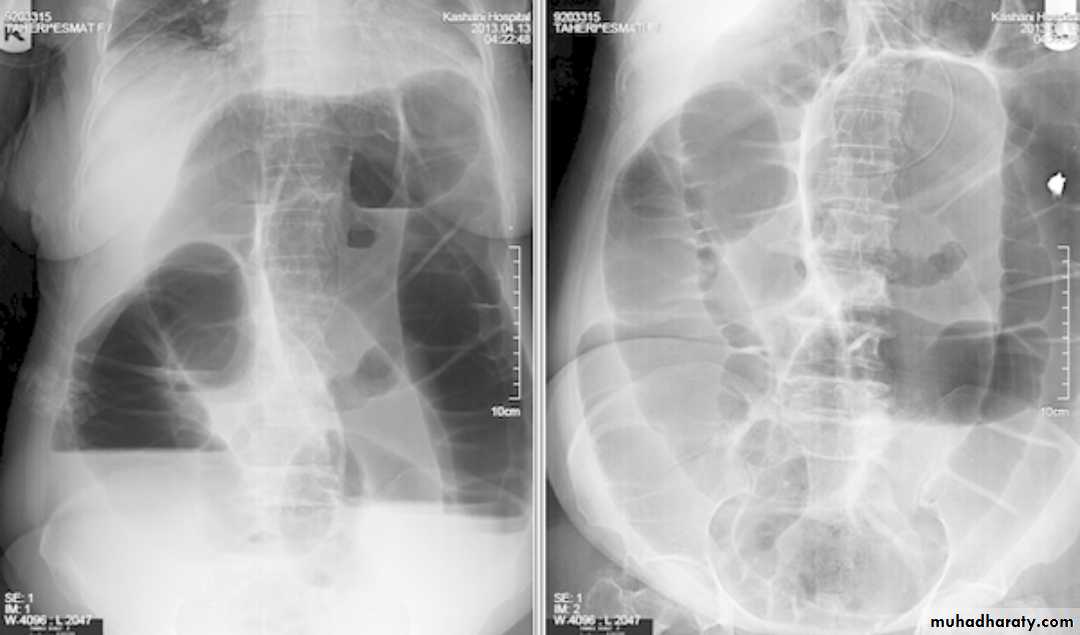

Intussusceptions occurs when one segment of bowel is pulled into itself (or a neighboring loop of bowel) It is an important cause of an acute abdomen in childrenIntussusceptions may also occur in the adult population where it is usually caused by a focal lesion acting as a lead point.

Radiographic features

Intussusceptions can occur essentially anywhere, in children there is a strong predilection for the ileo colic region

Abdominal plain film

Abdominal x-rays may demonstrate an elongated soft tissue mass (typically in the right upper quadrant in children) with a bowel obstruction proximal to it.

contrast enema

A contrast enema remains the gold standard, demonstrating the intussusceptions as an occluding mass prolapsing into the lumen, giving the "coiled spring ” appearance .The main contra-indication for an enema is a perforation

Contrast enema is diagnostic & therapeutic